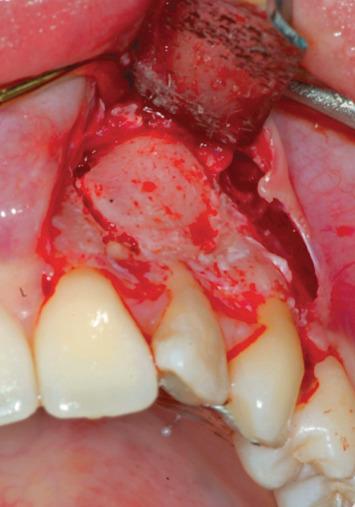

The aim of this case report was to evaluate the efficacy of a new platelet-rich plasma preparation and its regenerative capacity of bone periapical tissue for the treatment of a very compromised endodontic treated tooth, with a periapical lesion of 1.5 cm in diameter, using a pure platelet concentrate. This is made without the use of anticoagulant or any type of activator, e.g., bovine thrombin, calcium chloride. For this reason, it has been called "Pure"; it is the B.P.F.C.® Bio-Plasma® with Pure Growth Factors (BioPlasma®) designed and developed by Dr. Raffaello Viganò. The patient has read and signed a written consent form. The study protocol was approved by the Ethics Committee for Human Studies, University of Varese. X-ray at 2 and 6 months and 4 years after endodontic surgery demonstrated the success of the treatment.

本病例报告的目的是评估一种新型富血小板血浆制剂的疗效及其对根尖周组织的再生能力,该制剂为纯血小板浓缩物,用于治疗一颗根管治疗后严重受损且根尖周病变直径达1.5厘米的牙齿。该制剂的制备不使用抗凝剂或任何类型的激活剂,如牛凝血酶、氯化钙。因此,它被称为“纯”;它是由拉斐尔洛·维加诺博士设计和研发的含有纯生长因子的B.P.F.C.®生物血浆®(BioPlasma®)。患者已阅读并签署了书面知情同意书。该研究方案已获得瓦雷泽大学人体研究伦理委员会的批准。根管治疗术后2个月、6个月和4年的X线检查显示治疗成功。